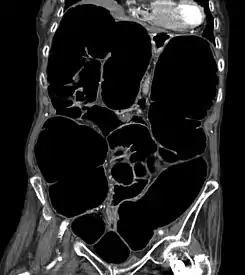

Tomografía computarizada que muestra una sección coronal del abdomen de una anciana con síndrome de Ogilvie